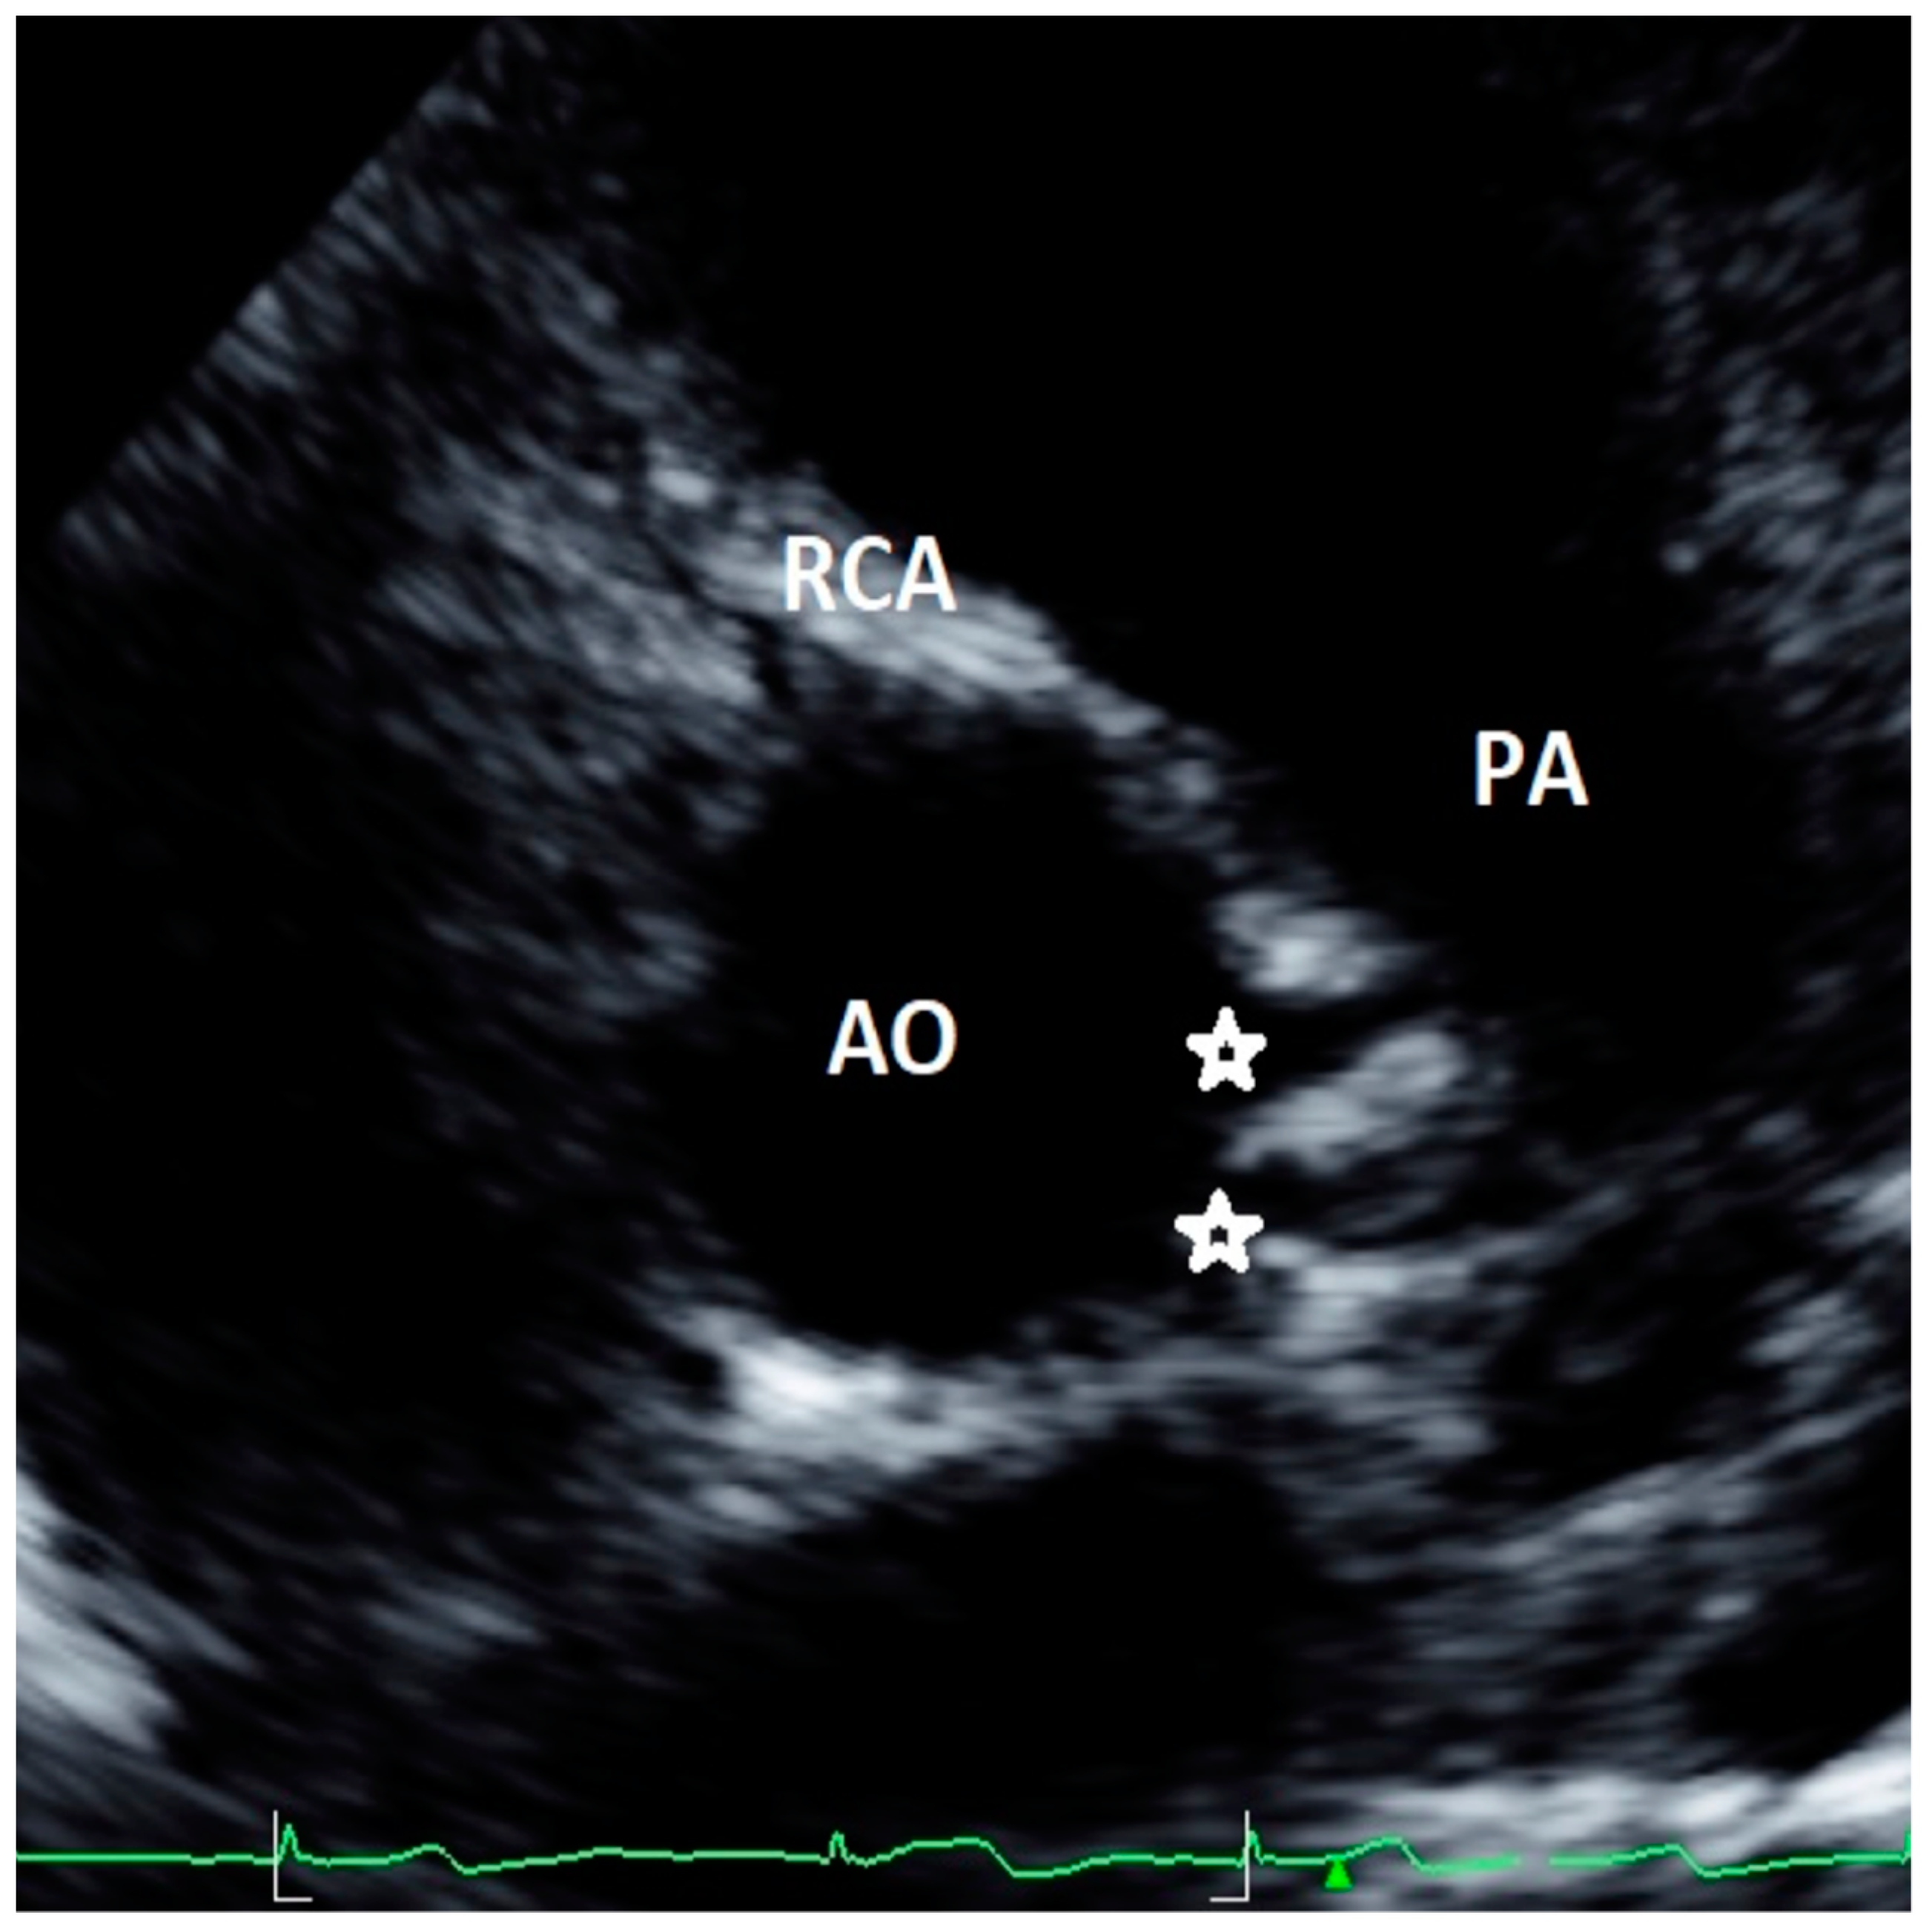

Figure 4. Modified apical 5-chamber view showing high take-off of left coronary artery (asterisk). This is a case of an asymptomatic 14-year-old female, with incidental diagnosis of bicuspid aortic valve. Ao = aorta, LCA = left common coronary artery, LV = left ventricle; PM = papillary muscle.

Discrepancies exist in the definition of major and minor AAOCAs, especially regarding the classification of a high take-off of coronary artery origin. Unfortunately, limited echocardiographic data are currently available in the literature [13,14,23]. Furthermore, most of the CT studies adopted a different definition as compared to echocardiographic articles. Indeed, in most cases, CT studies defined high take-off as a height >1 cm or >20% the depth of the sinus above STJ [26], a height >0.25 cm above the sinutubular junction, and a minority any height above the STJ [26]. Echocardiographic studies all used the latter definition, identifying the high take-off as an origin above or distal to the STJ [13,14,23]. The use of different cut-offs to define a high take-off has the consequence of affecting prevalence [33]; indeed, in CT studies where the definition of a height >1 cm or >20% the depth of the sinus above sinutubular junction was used, the incidence of RCA high take-off was 0.202%. Conversely, in those that employed a height >0.25 cm above the sinutubular junction as a definition, it decreased to 0.199% [33]. When the high take-off of RCA was defined as any height of origin above STJ, the prevalence of this defect increased [33] up to 0.364% [26]. In echocardiographic studies that used the latter definition, the reported incidence of RCA high take-off was even higher than in CT studies, ranging from 0.36% [23] to 1.14% [13]. This definition may overestimate the prevalence of high take-off but, most importantly, it may have the consequence to classify benign variants as malignant anomalies potentially at risk of SCD [33]. As recently reviewed [26], 3 of 12,899 (0.023%) cases of high take-off coronaries that originated more than one centimeter above the sinutubular junction were associated with SCD. Notably, although preferable in adults, the use of fixed criteria (such as 1 cm above the sinutubular junction) may have relevant limitations in children where aortic dimensions are smaller than in adults; therefore, some authors [44] proposed the adoption of relative criteria, such as coronary orifices that arise 120% or more of the depth of the sinus of Valsalva or 20% or more the depth of the sinus above the STJ. A comprehensive evaluation of a high take-off of coronary arteries should also include other important characteristics, such as the presence of slit-like ostium, stenosis, the interarterial course, and intramural course [26,33,34,35]. Notably, a high take-off associated with acute angulation from the aorta, an intramural or an interarterial course comprising 4% of the defects, are more at risk for the development of SCD [26]. This specific characteristic may be studied by echocardiography [13], but this imaging technique has inherent limitations for an accurate definition of these characteristics that need a comprehensive multimodality approach for their definition, as suggested by the current recommendations [26]. Furthermore, based on previously published studies, no clear indications exist for the appropriate acoustic window to be used for other coronary anomalies, such as the high take-off of coronary arteries, and particularly for LCA. Current recommendations [26] suggest using a coronal subcostal view to visualize LCA origin; however this window can be easily utilized only in neonates and children. We propose in this article an additional acoustic window that may allow for evaluation of high take-off of LCA by using a modified apical five-chamber view (see Figure 4). So far, we have tested this projection in a limited number of cases with suspicion of LCA high take-off or when origin of LCA was not seen by conventional short-axis and parasternal long-axis views, with encouraging results.